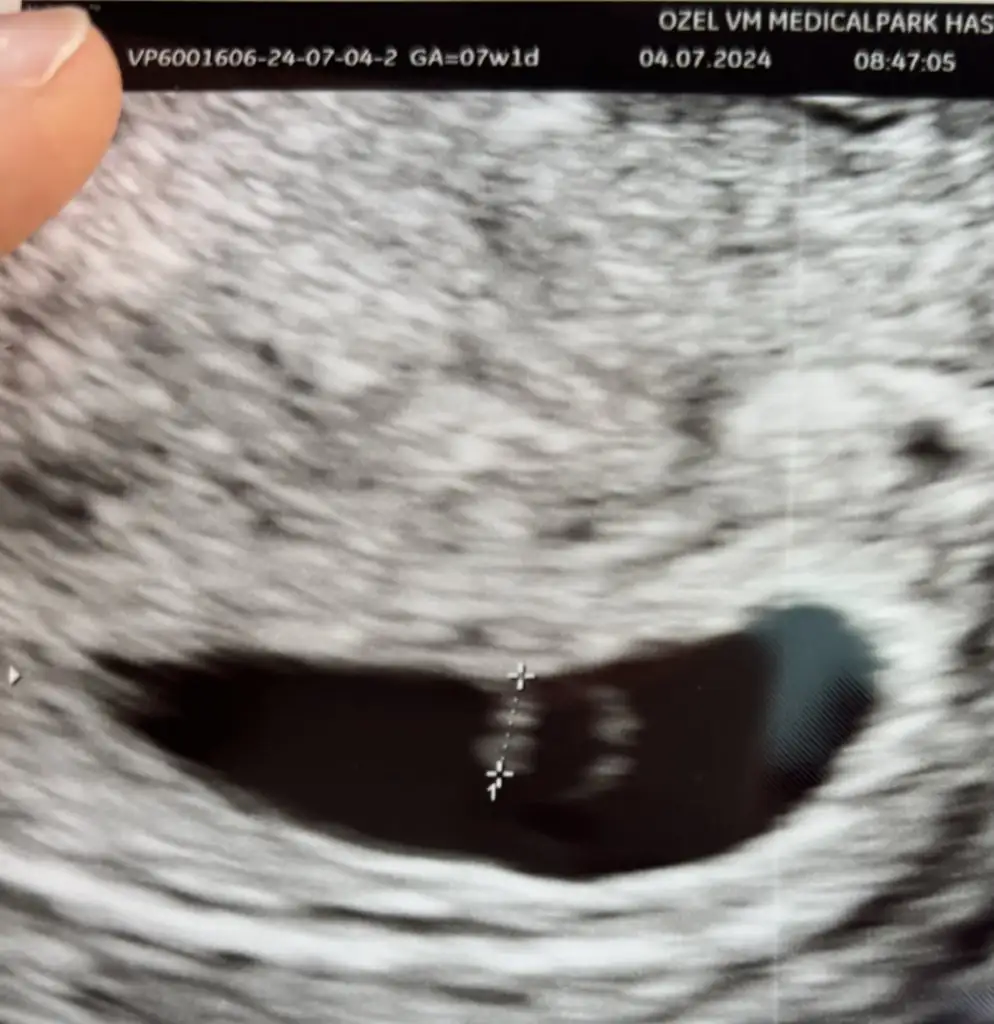

Kızlar simdi muayeneden cıktım . Kese şekli yolk normal gebelik belirtileri de normal ama embriyo çok küçük kalp atımı da yavaş dedi korkutmamaya çalışıyordu bence cok dıkkatlı konuşuyordu doktorum haftaya muayeneye cagırdı. Ya gec dollendi gec gelisiyor ya da takip edicez bu kalp atımının yavaş olması beni biraz endişelendirdi dedi. Böyle bişey yasayan var mı ya .doktorum bugun tatile gidiyor kanama vs olursa gel mutlaka dedi .burdan düzeledebilir takıpte kalıcaz dedi.bunu yaşayan var mı ya 😢sizi de uzmek istemezdim ama kusura bakmayın

• IMG_7057.webp

IMG_7057.webp

35,7 KB · Görüntüleme: 71